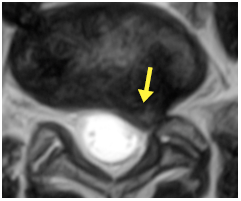

![]() 圖5B. 相同磁力共振掃描的水平平面圖像,顯示在 L5 / S1 位置出現椎間盤突出,並擠壓左面 S1 神經(箭咀所示)。 |